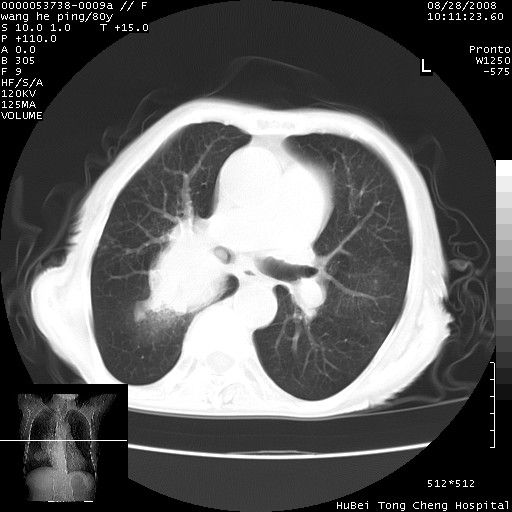

以下是引用黑白光影在2008-8-28 22:33:00的发言:[br]右肺中央型肺癌伴阻塞性肺炎,肺癌肺转移。

以下是引用lshx在2008-8-28 22:06:00的发言:[br]1.右肺中心型肺癌伴阻塞性肺炎,不除外双 肺早期转移。[br]2.心包积液。

以下是引用随光逐影在2008-8-29 7:40:00的发言:[br]1)右肺中心型肺癌伴阻塞性肺炎,肺内转移。2)心包积液(少量)。

以下是引用wqs571018在2008-8-28 21:56:00的发言:[br]右肺中心型肺癌伴阻塞性肺炎可能。

以下是引用liuyue在2008-8-28 22:46:00的发言:[br]1.右肺中心型肺癌伴阻塞性肺炎。[br]2.心包积液(少量)。